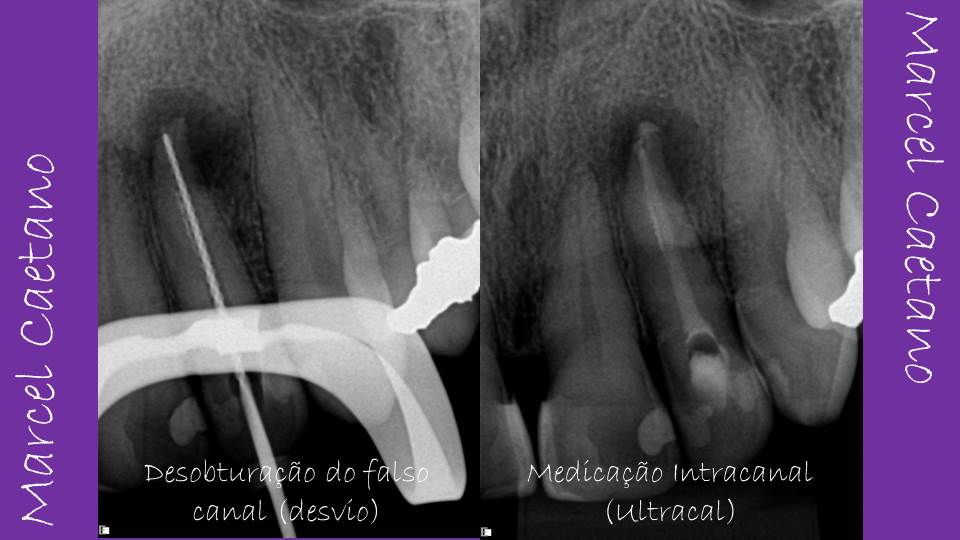

Usei a estratégia de remover o material obturador até o ponto de início da curvatura apical, para então tentar a partir daquele ponto retomar a trajetória original do canal e somente depois de estabelecido o caminho original do canal é que concluí a remoção do material obturador que estava presente no desvio. O objetivo desta manobra era evitar que as limas seguissem o caminho do desvio.

É importante destacar que as limas manuais foram imprescindíveis na fase da desobturação e na tarefa de retomar o caminho original do canal. Interessante também foi o fato de ter conseguido realizar a odontometria eletrônica, tanto com a lima no desvio quanto com a lima no canal original.

Após manutenção do canal preenchido com hidróxido de cálcio por um período de 2 meses (2 trocas neste período), decidi por finalizar o caso com a obturação definitiva do canal. Minha intenção inicial era adaptar o cone na trajetória original do canal, tentando pré-curvar o cone, inclusive usando o artifício de congelar o cone de guta-percha usando o gás refrigerante, mas o cone não seguia a trajetória original do canal, sempre seguindo para a área desviada. Deste modo, tive que travar o cone justamente no ponto de bifurcação desvio/canal e obturar.